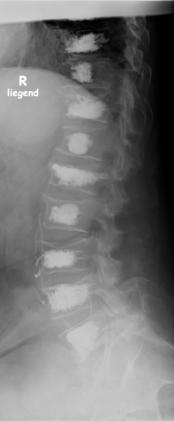

Definition nach WHO Die Osteoporose «Knochenschwund» oder «poröse Knochen» ist eine Erkrankung des Skelettsystems, die mit einem Verlust bzw. einer Verminderung von Knochensubstanz und Knochenstruktur einhergeht und infolge dessen zu einer erhöhten Anfälligkeit für Knochenbrüche führt. Osteoporose ist eine immer häufiger gestellte Diagnose. Ein Grund ist die zunehmend ältere Bevölkeung. Osteoporose ist die am meisten auftretende Knochenkrankheit im höheren Alter. Gründe für eine Erkrankung an Osteoporose sind u.a. die Ernährung mit Tendenz zur Übersäuerung, Umweltbelastungen mit insbesondere sich im Knochen ablagernden Schwermetallen, Medikamente, Vitamin-D-Mangel und mangelnde Bewegung. Häufiste Auswirkungen der Osteoporose: Wirbelkörper-Einbrüche (Sinterungen) Hüftgelenksnahe Oberschenkelknochenbrüche (u. a. Schenkelhalsfraktur) Handgelenksnahe Speichenbrüche (distale Radiusfraktur) Oberarmkopfbruch (subcapitale Humerusfraktur) Beckenbrüche Neigung zu Frakturen an anderen Stellen des Skeletts.